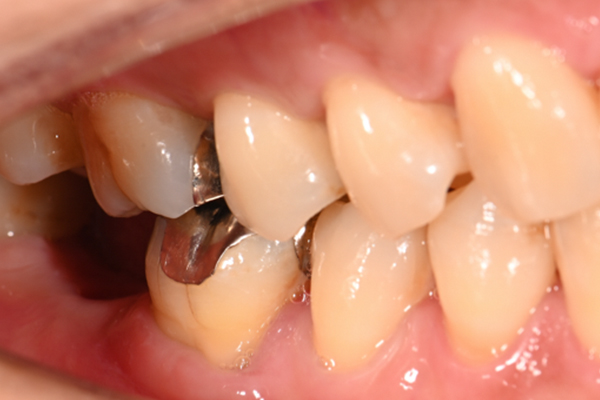

| 主訴 | 右下の奥歯が痛い |

|---|---|

| 治療内容 | 右下奥歯が割れていたため抜歯、その後インプラント治療を行った。(左の写真は抜歯後の写真) |

| 治療期間 | 4ヶ月 |

| 治療費 | 41万5千円 |

| 治療 リスク | 抜歯後インプラントの処置まで3ヶ月程度治癒期間(骨ができるまでの期間)が必要なことがあります。 |